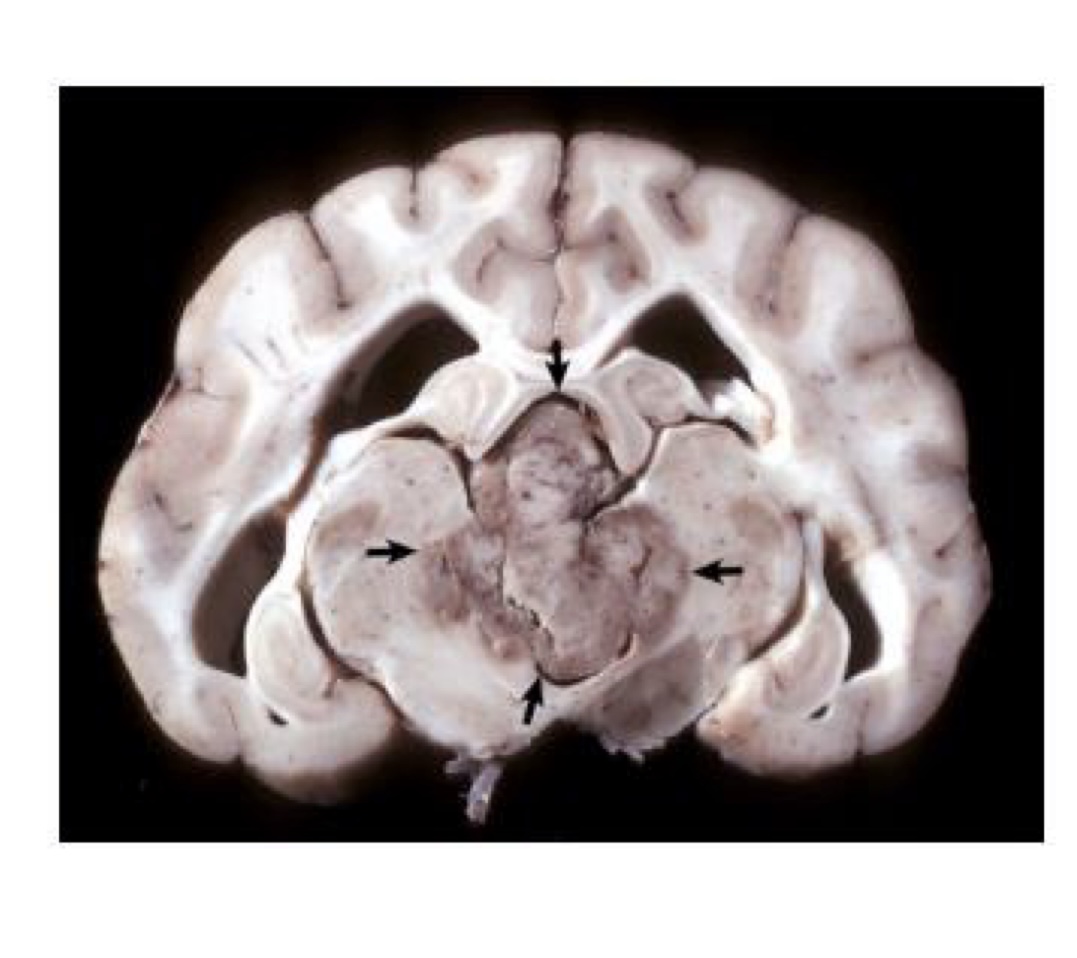

what is this?

medulloblastoma → white to tan, homogenous mass that compresses the cerebellum and brainstem